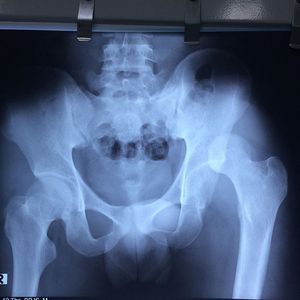

Neglected posterior dislocation of the hip

Orthopaedics

Reduction

Hipdislocation